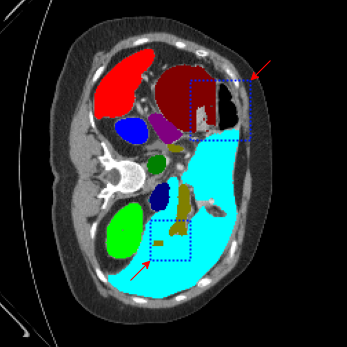

| Ground Truth | LoGoNet | DiNTS Search |

|---|---|---|

![]() |

We begin by qualitatively inspecting our model. Figure 3 compares the output of LoGoNet to the best performing baseline model in BTCV dataset, i.e., DiNTS Search (more qualitative comparisons can be found in appendix section 11). We see that our model particularly excels in segmenting organ boundaries. This can be attributed to our effective strategy for extracting local-range dependencies, which plays a crucial role in extracting details from input data. Our model’s adeptness in capturing long-range dependencies allows it to grasp contextual information that extends over significant distances within the data. Simultaneously, its proficiency in handling short-range dependencies ensures precision in capturing localized patterns.